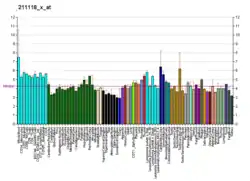

Tissue distribution

ERβ is expressed by many tissues including the uterus,[23] blood monocytes and tissue macrophages, colonic and pulmonary epithelial cells and in prostatic epithelium and in malignant counterparts of these tissues. Also, ERβ is found throughout the brain at different concentrations in different neuron clusters.[24][25] ERβ is also highly expressed in normal breast epithelium, although its expression declines with cancer progression.[26] ERβ is expressed in all subtypes of breast cancer.[27] Controversy regarding ERβ protein expression has hindered study of ERβ, but highly sensitive monoclonal antibodies have been produced and well-validated to address these issues.[28]